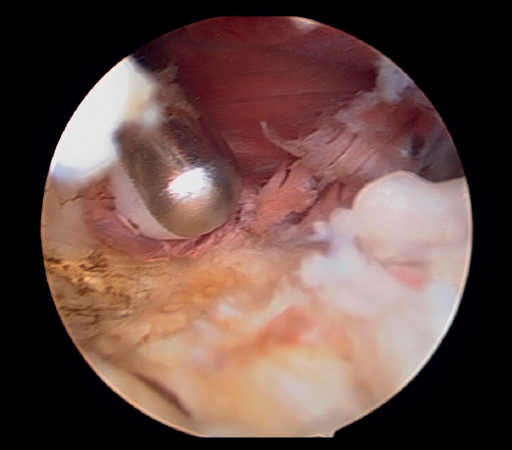

En primer lugar, se realiza el portal anteromedial de visión, incidiendo únicamente la piel y realizando disección roma con un mosquito recto. A continuación, se introduce la vaina del artroscopio, atravesando de forma anterior y proximal el septo fibromuscular medial, en dirección a la cabeza del radio, de forma posterior y distal, para evitar lesionar el nervio cubital y el paquete vascular anterior del codo. Una vez introducida la óptica en el portal medial, se procede a realizar el portal lateral proximal como portal de trabajo. Se realiza bajo visión directa, utilizando como guía una aguja intramuscular de fuera a dentro, para localizar el punto de entrada que permita mejor ángulo de trabajo (Figura 4). Posteriormente, se incide en la piel y se realiza disección roma con un mosquito recto para entrar en la articulación (Figura 5).

Figura 5. Realización del portal lateral (paciente en decúbito lateral, codo derecho, visión desde el portal medial).